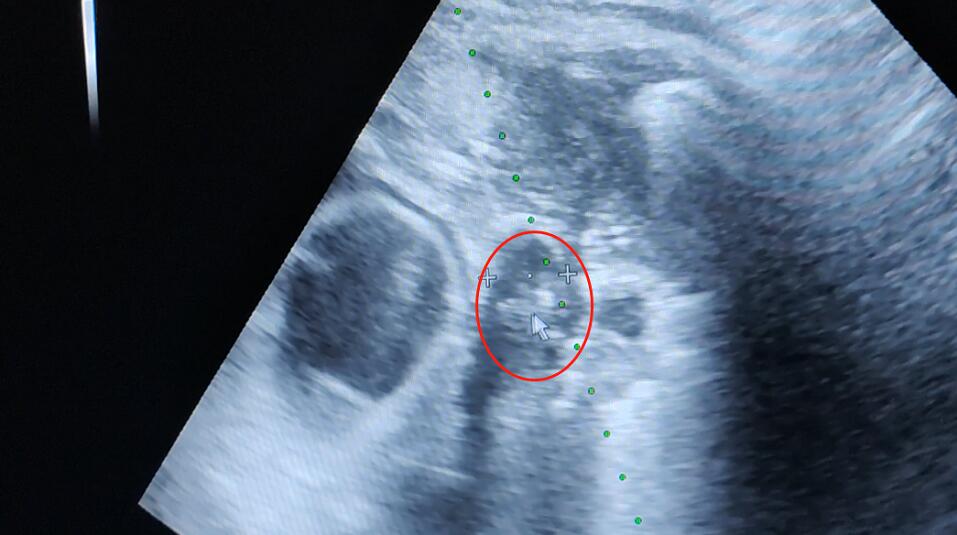

手术当天,在彩超实时引导下,以右中肺肿瘤为靶区,用18G活检枪穿刺到靶区,取出肿瘤组织送病理检查;再用超冷刀精准插入肿瘤组织,彩超扫描到位后100%气量冷冻15分钟两个循环,温度降至-195℃~-170℃直至见冰球覆盖靶区,复温后拔除超冷刀,包扎穿刺点,手术顺利完成。

治疗中冰球形成